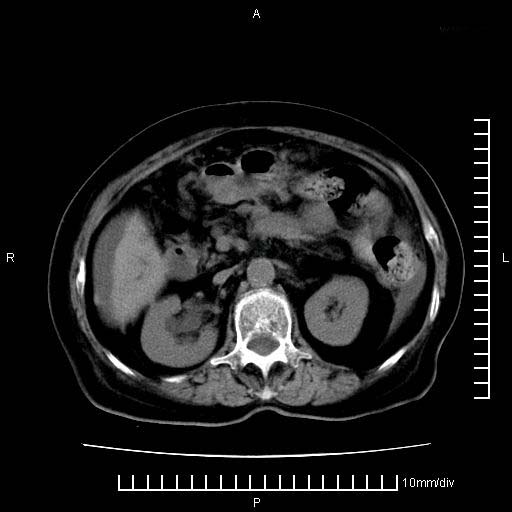

标题: CT28280:腹部增强:女性,80岁

上腹疼痛月余,外院核磁诊断胰腺癌。现临床示右下腹可明显触及包块,可片子上怎么没有看到?

1.胰腺颈体部癌。

2。腹腔积液。

胰腺体部癌累及周围器官,腹膜、粘连

胰腺体部癌累及周围器官,腹膜、粘连,临床摸到的可能是粘的组织

胰腺结构模糊,胰尾部见囊性包块,周围脂肪密度增高,左肾前筋膜增厚,胸水、腹水。不符合胰腺ca伴腹膜腔转移。考虑胰腺炎伴假性囊肿形成、胸腹腔积液。

1、考虑胰腺癌伴腹膜腔转移,胸腹水。

1)考虑胰腺癌并胰腺假性囊肿形成。2)肝内低密度灶,不排除转移。3)右肾盂积水。4)腹水。5)右侧胸腔积液并右肺下叶部分膨胀不全。